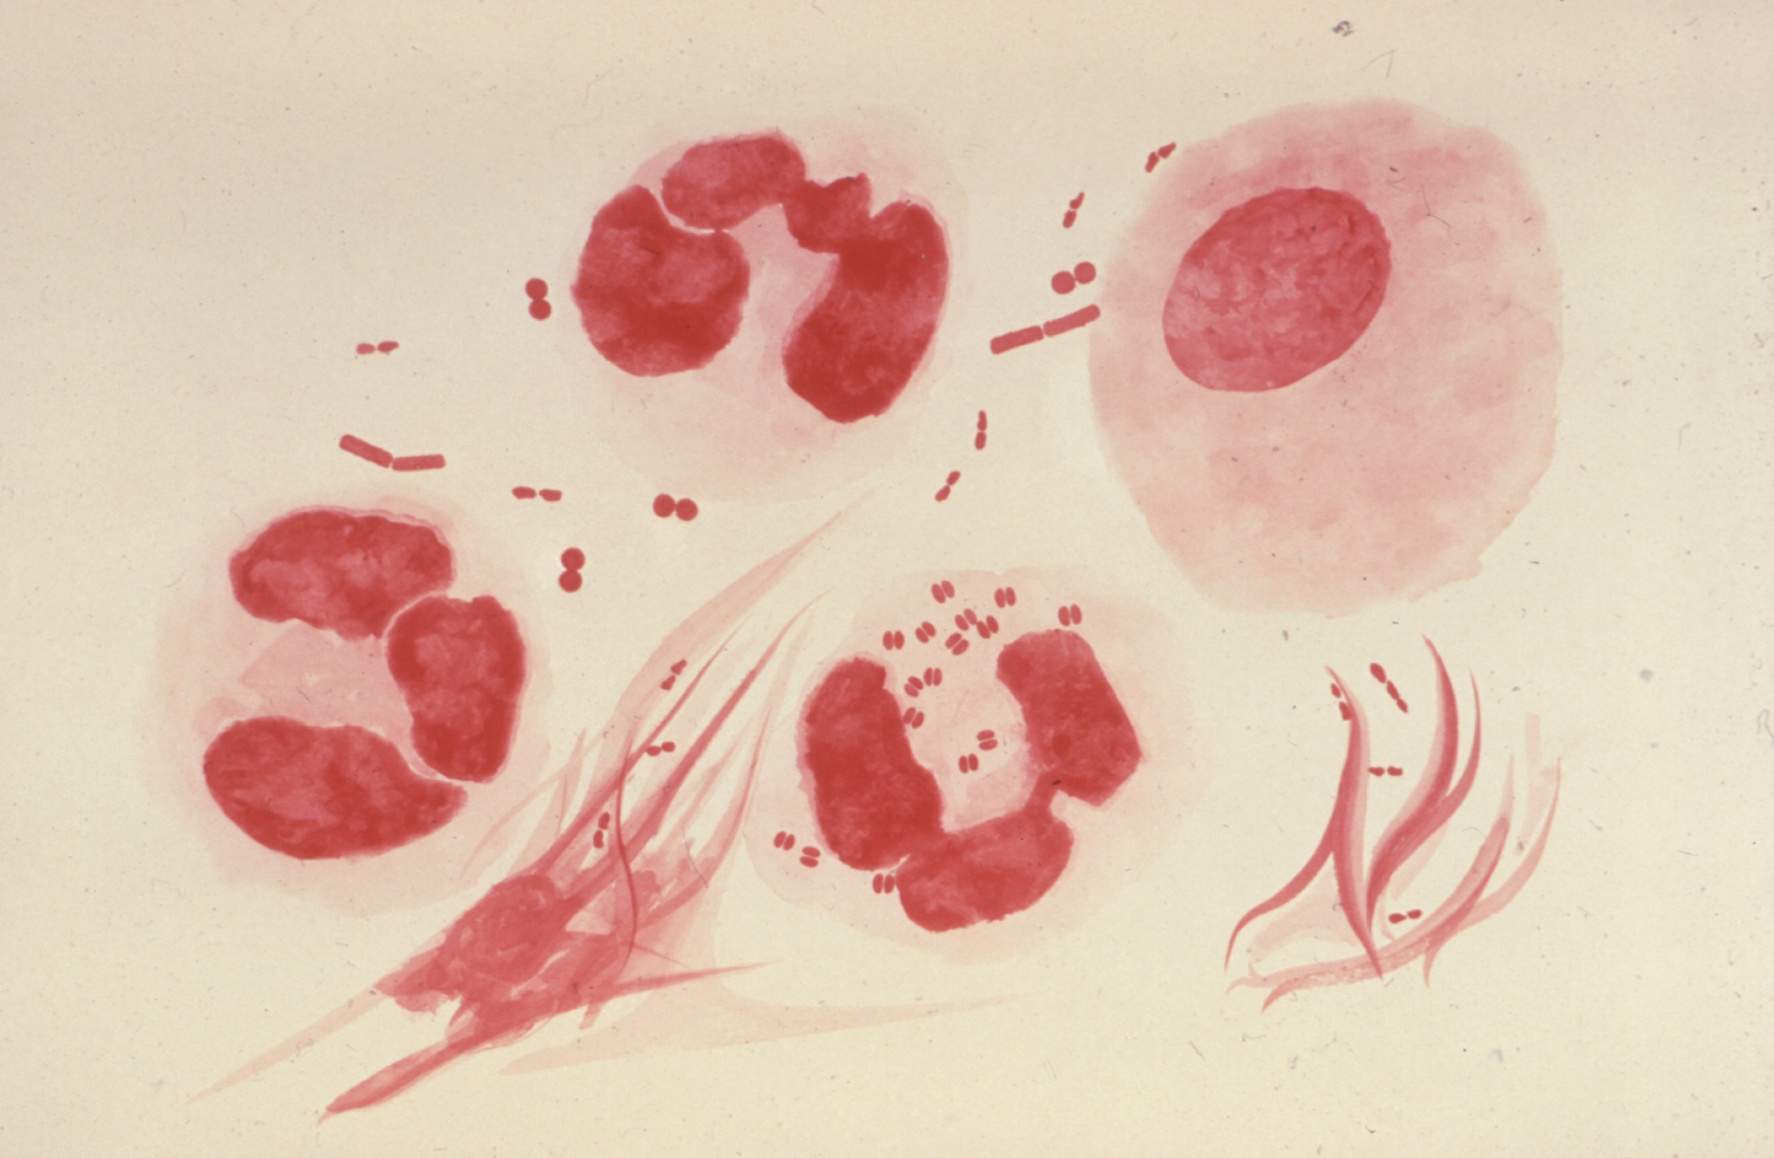

Ante el aumento de casos de resistencia a los antibióticos, hacen falta nuevos tratamientos para la gonorrea

Lunes, 14 de abril de 2025 - 18:44